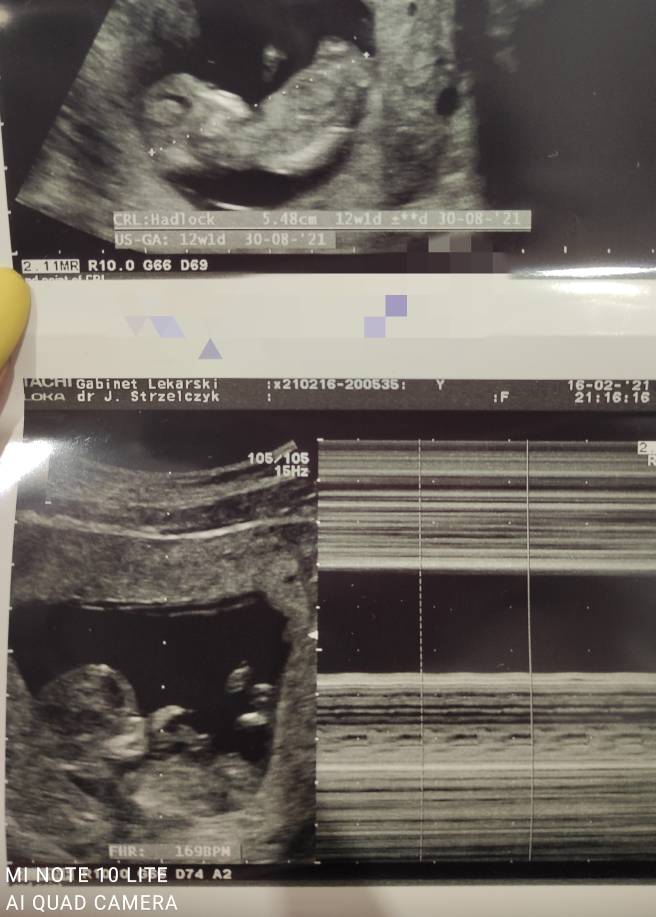

wrześniowe mamy 2021

Hej, jutro muszę zrobić pierwsze badania i oczywiście zgubiłam kartkę.. Jakie pierwsze badania robiłyscie ?

Pierwsze na nfz miałam morfologia, glukoza, mocz.

Potem poszlam z tymi wynikami na pierwsza prywatną wizytę i dostałam to:

1. Grupa krwi rh

2. Tsh

3. Usr

4. Toxo IgM

5. Toxo IgG

6. Pciała anty HIV

7. Pciała anty HCV